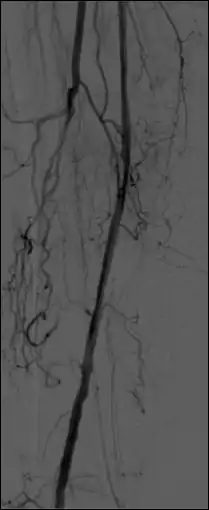

- The temporal-averaging feature of digital noise reduction can also be used for image presentation purposes so that the time course of the movement of contrast medium during a study can be displayed using just one image - see an example in Figure 7.4 from the peripheral study shown above - instead of a sequence of numerous images. Such an image is sometimes referred to as a Vascular Trace.

- One method of temporal filtration, referred to as Integrated Mask-Mode DSA involves adding (also called integrating) a number of images, acquired prior to the arrival of the contrast medium, to form an integrated mask image and adding a number of peak-opacification images to form an integrated live image. This is the process that was used to generate the vascular trace image in Figure 7.4. Thus, when four images are used to generate each integrated mask and live images, eight of the 25 images are now used in the subtraction process and, as a result, only 68% of the dose is wasted, and a subtraction image with lower noise results.

- A second method of temporal filtration, referred to as Matched Filtration, attempts to utilise all 25 images. It involves using information derived from the temporal variation in the concentration of contrast medium in the blood vessel of interest. This information can be obtained by using densitometric analysis software to plot the dilution curve for a region of the blood vessel, i.e. a plot of the time course of the contrast medium. This dilution curve is then used to define a range of weighting factors that are applied to each image in the sequence and the resulting images are simply added together. The processed DSA image has a relatively high SNR as a result of the integration of images. Further refinement of such filters can be used to colour-code parameters such as the time-of-arrival and the time-to-peak opacification, into the displayed image data. Although Matched Filtration has been shown both theoretically and experimentally to generate a DSA imaging process with good image quality and dose utilisation characteristics[27], it has not gained widespread clinical application.

- Additional processes involve Bolus Chasing, Rotational Angiography and Volume Tomographic Angiography. Bolus Chasing[28] has been found to be particularly helpful in peripheral angiography, for example. Here, the progress of the contrast medium is tracked automatically and used to increment the table and/or XRT/image receptor movement to the next anatomical region. The subsequent set of subtraction images can then be used to construct a composite image of the peripheral vasculature. In Rotational Angiography[29], a C-arm assembly, for example, can be caused to rotate at 10 - 30 degrees per second during the imaging sequence. Subsequent dynamic display of the subtraction images can be used to generate a perceived 3D presentation so that complex relationships within the vasculature can be more readily appreciated. Volume Tomographic Angiography[30] is similar to Computed Tomography (CT) where the C-arm is rotated around the patient during the imaging sequence. The image data is subject to a volume reconstruction algorithm which permits generation of three-dimensional images of the opacified vasculature. We will consider this latter process in more detail below.